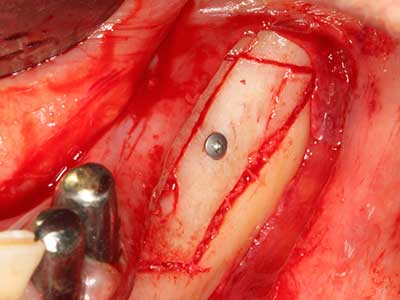

Bei der Knochenblockentnahme zeigen sich weitere Vorteile für die Piezochirurgie: Neben der bereits beschriebenen hohen Präzision bei der Osteotomie stellt sich gerade die Verwendung der dünnen Sägespitzen als besonders materialschonend heraus. Bei der Verwendung insbesondere von Lindemannfräsen sind mit deutlich höheren Entnahmeverlusten durch die dickere Instrumentenspitze zu rechnen (Lakshmiganthan, Gokulanathan et al. 2012). Die insbesondere bei retromolar entnommenen Blocktransplantaten notwendige basale Abtrennung wird durch speziell hierfür vorgesehene rechtwinklige Sägen erleichtert, so dass die Piezochirurgie als präzises, übersichtliches und sicheres Verfahren zur retromolaren Knochenblockgewinnung angesehen wird (Happe 2007) (Abb. 1-12).

Sollen chirurgische Eingriffe mit unmittelbarer Knochenbeziehung an empfindlichen Strukturen wie Blutgefäßen oder Nerven erfolgen, so bergen rotierende Instrumente ein erhebliches Potential an iatrogener Schädigung. Gerade bei Nervdarstellungen nach iatrogener Schädigung, oder aber im Zuge einer Nervlateralisation für resektive und rekonstruktive Eingriffe oder Implantatinsertionen können piezoelektronische Geräte hilfreich sein Knochendeckel zu präparieren und nervnahe Hartgewebsanteile zu entfernen (Abb. 17-20). Ein leichter Kontakt des Nervstrangs zur Piezospitze bleibt dabei in der Regel folgenlos – allerdings kann eine unvorsichtige Vorgehensweise mit sägeartigen Bewegungen bzw. Ansätzen bei noch vorhandener knöcherner Unterlage durchaus temporäre oder aber auch permanente Nervschädigungen verursachen. Das Risiko einer solchen Schädigung wird jedoch als wesentliche geringer eingeschätzt als unter Anwendung von Säge- oder Fräsinstrumenten (Pereira, Gealh et al. 2014).

Weitere Einsatzgebiete ergeben sich in der Kieferhöhlenchirurgie: Hier können nach konzentrischer Präparation eines in der Regel trapezförmigen Knochendeckels der fazialen Kieferhöhlenwand Pathologien und Fremdkörper aus der Kieferhöhle entfernt werden. Der Knochendeckel wird nach Abschluss des intra-antralen Operationsanteils reponiert und durch Verkeilen oder adaptierende Nähte gegen Dislokation gesichert.